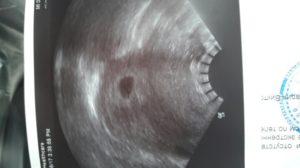

Если беременность 6 недель, коричневые выделения появились, постоянно мучают боли внизу живота, ухудшается общее состояние, необходимо сразу обратиться к врачу. При таких симптомах часто назначается УЗИ. При наличии беременности в матке причины такого состояния дополнительно выясняются. Если диагностирована внематочная беременность, ее необходимо устранить.

Причины этих явлений бывают опасными для здоровья мамы и плода. Но в любом случае нельзя впадать в панику, а нужно обратиться к врачу, пройти УЗИ и держать ситуацию под контролем. Четыре из пяти женщин, наблюдавших коричневые выделения на ранних сроках беременности, донашивают ее и рожают детей.

Редкая, но опасная ситуация – пузырный занос. При нем на УЗИ вместо плаценты в матке обнаруживают большое количество заполненных жидкостью пузырьков – кист. Выделения при беременности бывают коричневыми, желто-коричневыми, бурыми, с вкраплениями пузырьков. Женщины отмечают:

Поэтому откладывать визит к гинекологу нельзя. При появлении любых необычных симптомов следует идти к специалисту. Он проведет комплексное обследование, сделает УЗИ и возьмет анализы. Помните, что на раннем сроке болезнь легче поддается терапии.

Если боль ощущается все чаще, появились коричневые выделения, стоит сходить к гинекологу и сделать УЗИ. Если угроза прерывания подтвердилась, потребуется лечение в стационаре. Безотлагательная медицинская помощь необходима при наличии следующих симптомов:

К сожалению, для некоторых женщин эти коричневые выделения свидетельствуют о выкидыше. Врач оценивает состояние пациентки с помощью ультразвукового обследования. Дополнительно женщина сдает анализ крови на содержание особого гормона — хорионического гонадотропина (ХГЧ). Все эти показатели становятся основанием для амбулаторного лечения будущей мамы или ее госпитализации.

Осторожно! Нет особых симптомов, чтобы отличить внематочную беременность от воспаления придатков, поэтому поможет определить диагноз только УЗИ.